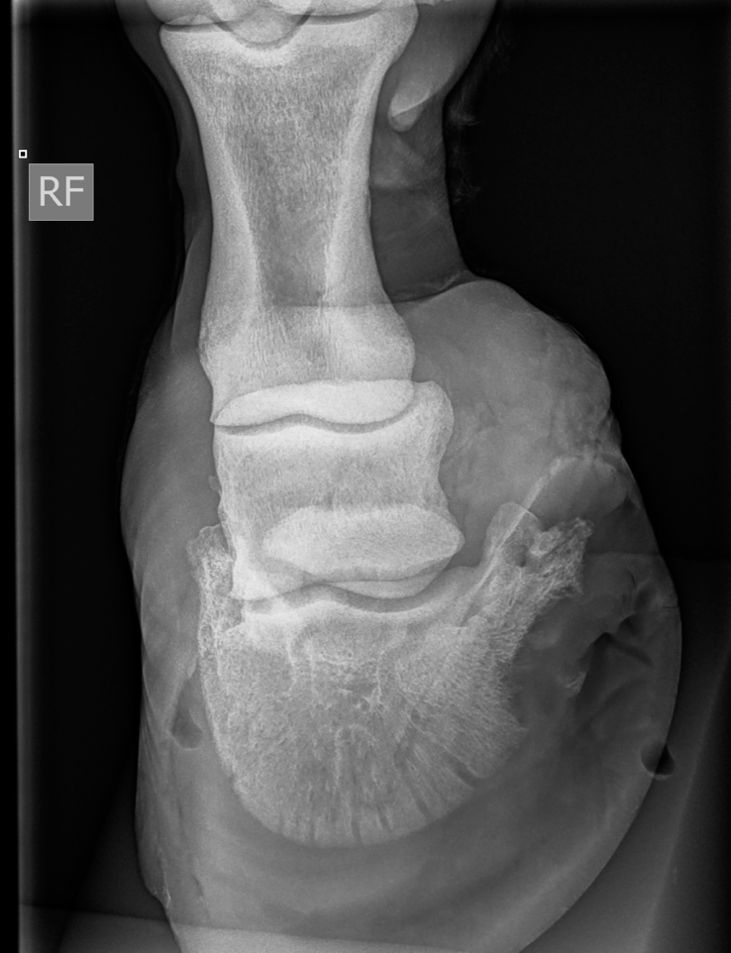

Volgende radiografische projecties (DPr-PaDiO en DMPr-PaLDiO) van de voet werd genomen.

- Groot en onregelmatig afgelijnd defect ter hoogte van de palmaromediale rand van het hoefbeen, over een dorsopalmaire afstand van circa 3 cm.

- Kleine, gemineraliseerde, onregelmatig en onscherpe opaciteit (ongeveer 6 mm) gesuperponeerd op het hoefkapsel en aangrenzend aan dit defect.

- Het hoefkapsel vertoont ter hoogte van deze regio een matig heterogeen aspect (gasopaciteiten en/of hoefdefect).